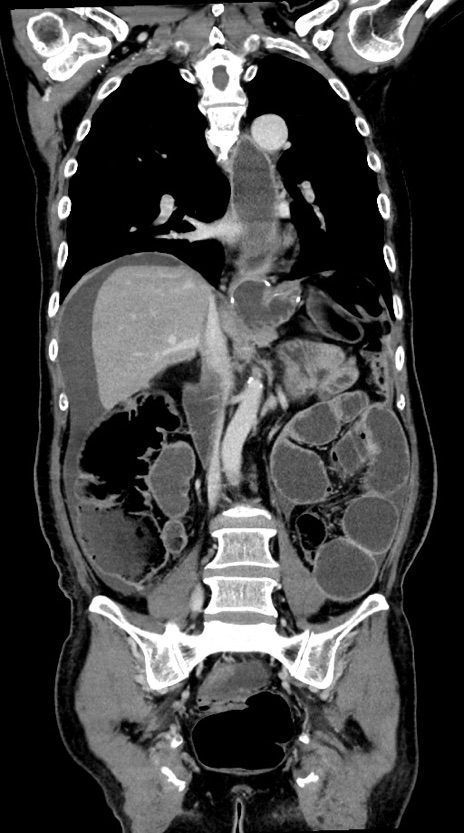

症例28(冠状断像)

【症例】60歳代男性

【主訴】嘔吐

【現病歴】胃癌にて胃全摘後。食思不振が悪化し、夜中に嘔吐することがある。

【既往歴】胃癌、胃全摘、脾摘、胆摘後

【データ】WBC 5900、CRP 10.56